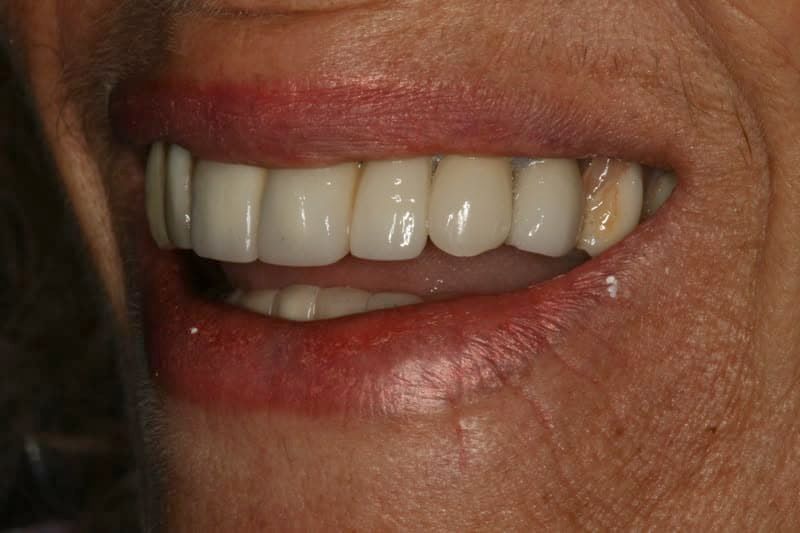

Our patient M., as we’ll call her, has been with our practice since late 2006. She had some well-done dental work many years before, including long PFM (Porcelain-fused-to-Metal) dental bridges. In the spring of 2008, however, she broke a big piece of porcelain off a top front tooth. The bright silver shining through really bothered her. She didn’t want to replace the whole thing, because it cost too much. I’d recently learned the “overcrown” technique through a professionals-only dental forum. Given it was the only option except for replacement, she let me try. I think you’ll agree – it turned out pretty well!

As of this blog publication date, that bridge repair with an overcrown is 11 years old, and it still looks great.